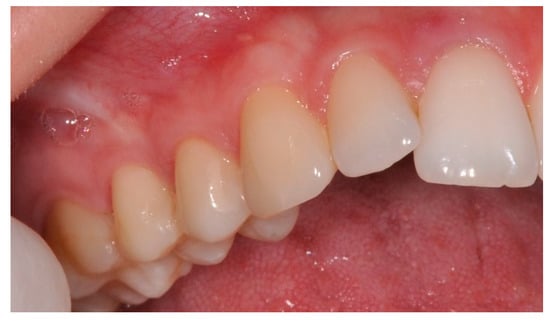

Laterally Positioned Flap Procedure with Augmented or Nonaugmented Palatal Connective Tissue Grafts in the Treatment of Multiple Adjacent Gingival Recessions: A Two-Year Follow-Up Study

:1. Introduction

2.3. Surgical Procedures